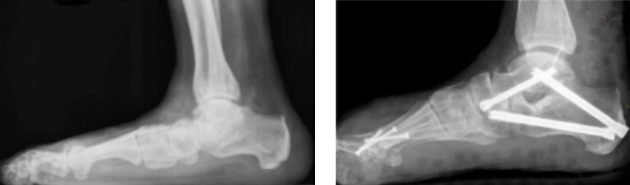

Bei Patienten mit Klumpfußfehlstellung z.B. nach Schlaganfällen oder anderen neurologischen Erkrankungen kann durch das Ablösen dieser Sehne am Kahnbein und den Transfer dieser Sehne auf den Fußrücken einerseits die pathologische Zugkraft erheblich reduziert und durch die Verlagerung in eine andere Zugrichtung gebracht werden, sodaß aus einer Beugesehne eine Strecksehne (Fußhebung) wird. Dabei wird die Sehne durch einen Tunnel zwischen Schien- und Wadenbein nach vorne vor das obere Sprunggelenk gezogen und über einen Anker oder einen Bohrkanal in einem der Keilbeine verankert.